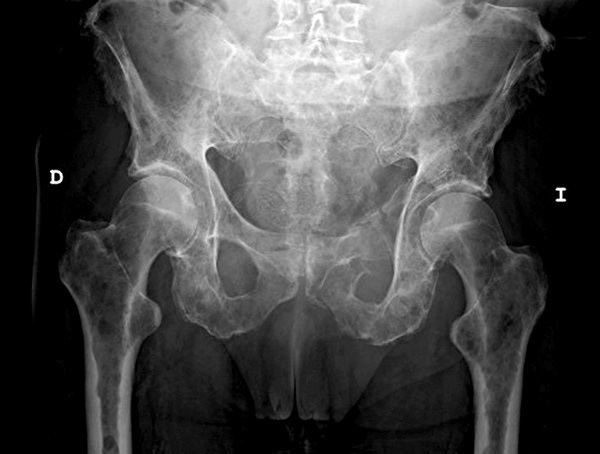

Una densitometría ósea realizada a los 15 años de edad, demostró una densidad mineral ósea lumbar (DMO) de 0,474 g/cm2 (Z-score: -6,43). Se trató con zolendronato durante una década, mejorando su DMO lumbar hasta 0,854 g/cm2. Pero, tras un año de abandonar el tratamiento, sufrió una fractura atípica diafisaria femoral, siendo entonces referido a nuestro servicio.

Se comenzó tratamiento con teriparatida subcutânea. Tras dos años de tratamiento, se detuvo la administración y se inició terapia con de-nosumab cada 6 meses, aumentando su DMO lumbar a 1,81 g/cm2 (Zscore: -0,4).